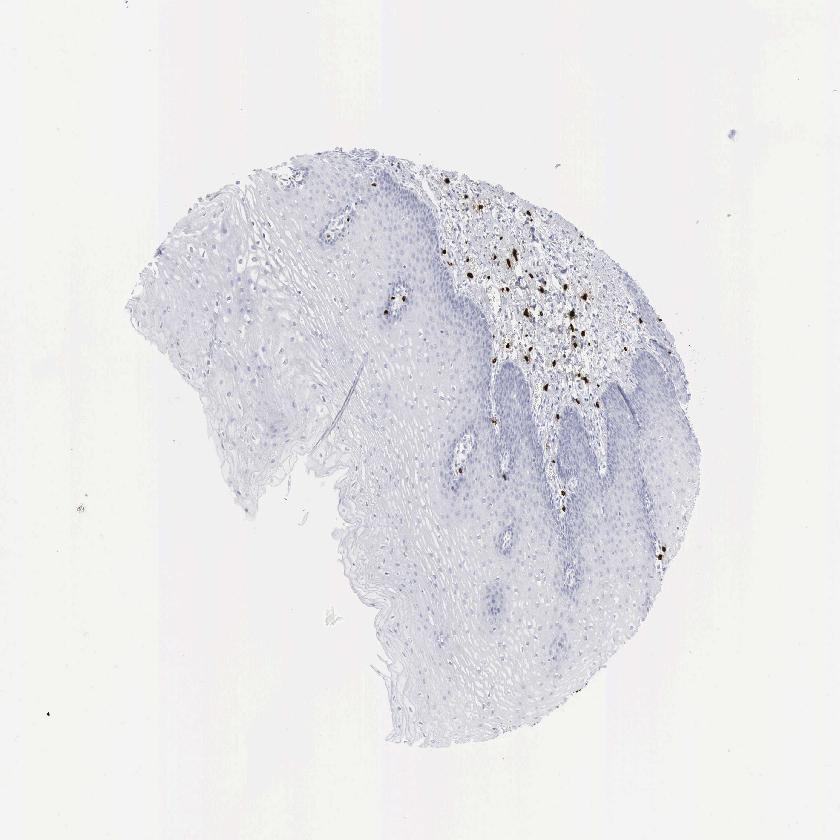

ESOPHAGUS - Antibody stainingi

Antibody staining in the annotated cell types in the current human tissue is reported as not detected, low, medium, or high, based on conventional immunohistochemistry profiling in selected tissues. This score is based on the combination of the staining intensity and fraction of stained cells.

Each image is clickable and will lead to virtual microscopy that enables deeper exploration of all samples and also displays staining intensity scores, fraction scores and subcellular localization as well as patient and tissue information for each sample.

Antibody HPA052634Antibody CAB000363

Squamous epithelial cells Not detectedNot detected